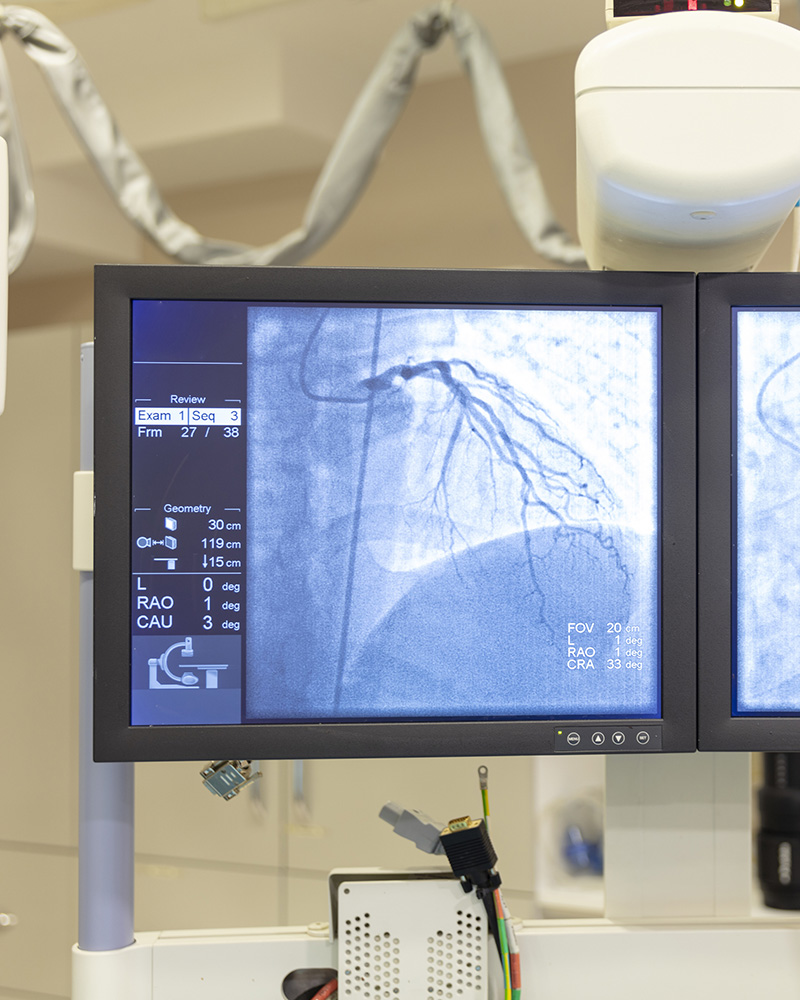

Using XRay Imaging For Cardiac Ablation A Modern Approach MedShun Cardiac Ablation Mater Private Mater private network, in partnership with boston scientific, has announced today that it is the first hospital network in ireland and within only 25 centres in the world to. The mater private was one of 17 european centres to take part in a breakthrough vistax trial* which showed that using new technology to treat atrial fibrillation has resulted in. Glover. Cardiac Ablation Mater Private.

From medshun.com